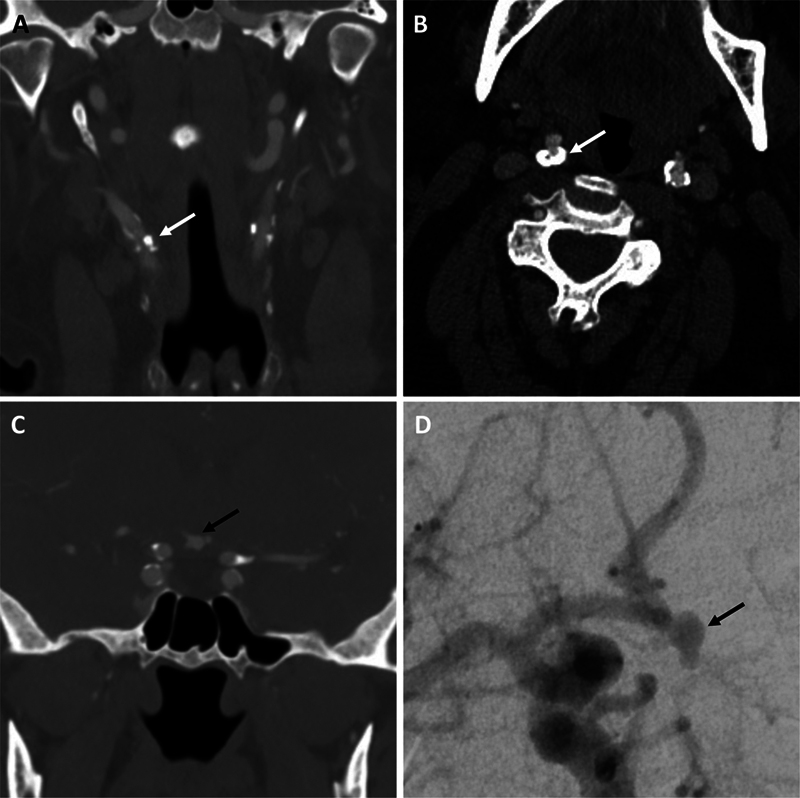

Introduction  The coexistence of carotid artery stenosis and a concomitant downstream ipsilateral unruptured intracranial aneurysm requires unique treatment considerations to balance the risk of thromboembolic complications from carotid artery stenosis and the risk of subarachnoid hemorrhage from intracranial aneurysm rupture. These considerations include the selection of optimal treatment modalities, the order and timing of interventions, and potential management of antiplatelet agents with endovascular approaches. We present strategies to optimize treatment in such a case. Case Report  We discuss the case of a 69-year-old woman with 90% stenosis of the right internal carotid artery and an ipsilateral, wide-necked, 4.8-mm, irregular-appearing right A1-2 junction aneurysm with an associated daughter sac. Open, endovascular, and mixed treatment strategies were considered. The patient selected and underwent a staged, open treatment approach with a carotid endarterectomy followed by a right craniotomy for microsurgical clipping of the aneurysm 5 days later. Both procedures were performed on daily full-dose aspirin without complications. On follow-up, the right carotid artery was widely patent, the aneurysm was secured, and the patient remained at her neurologic baseline. Discussion  The presented strategy for ipsilateral carotid artery stenosis and an unruptured intracranial aneurysm initially optimized cerebral perfusion to mitigate ischemic risks while permitting timely aneurysm intervention without a need for dual antiplatelet therapy or to traverse an earlier procedure site.